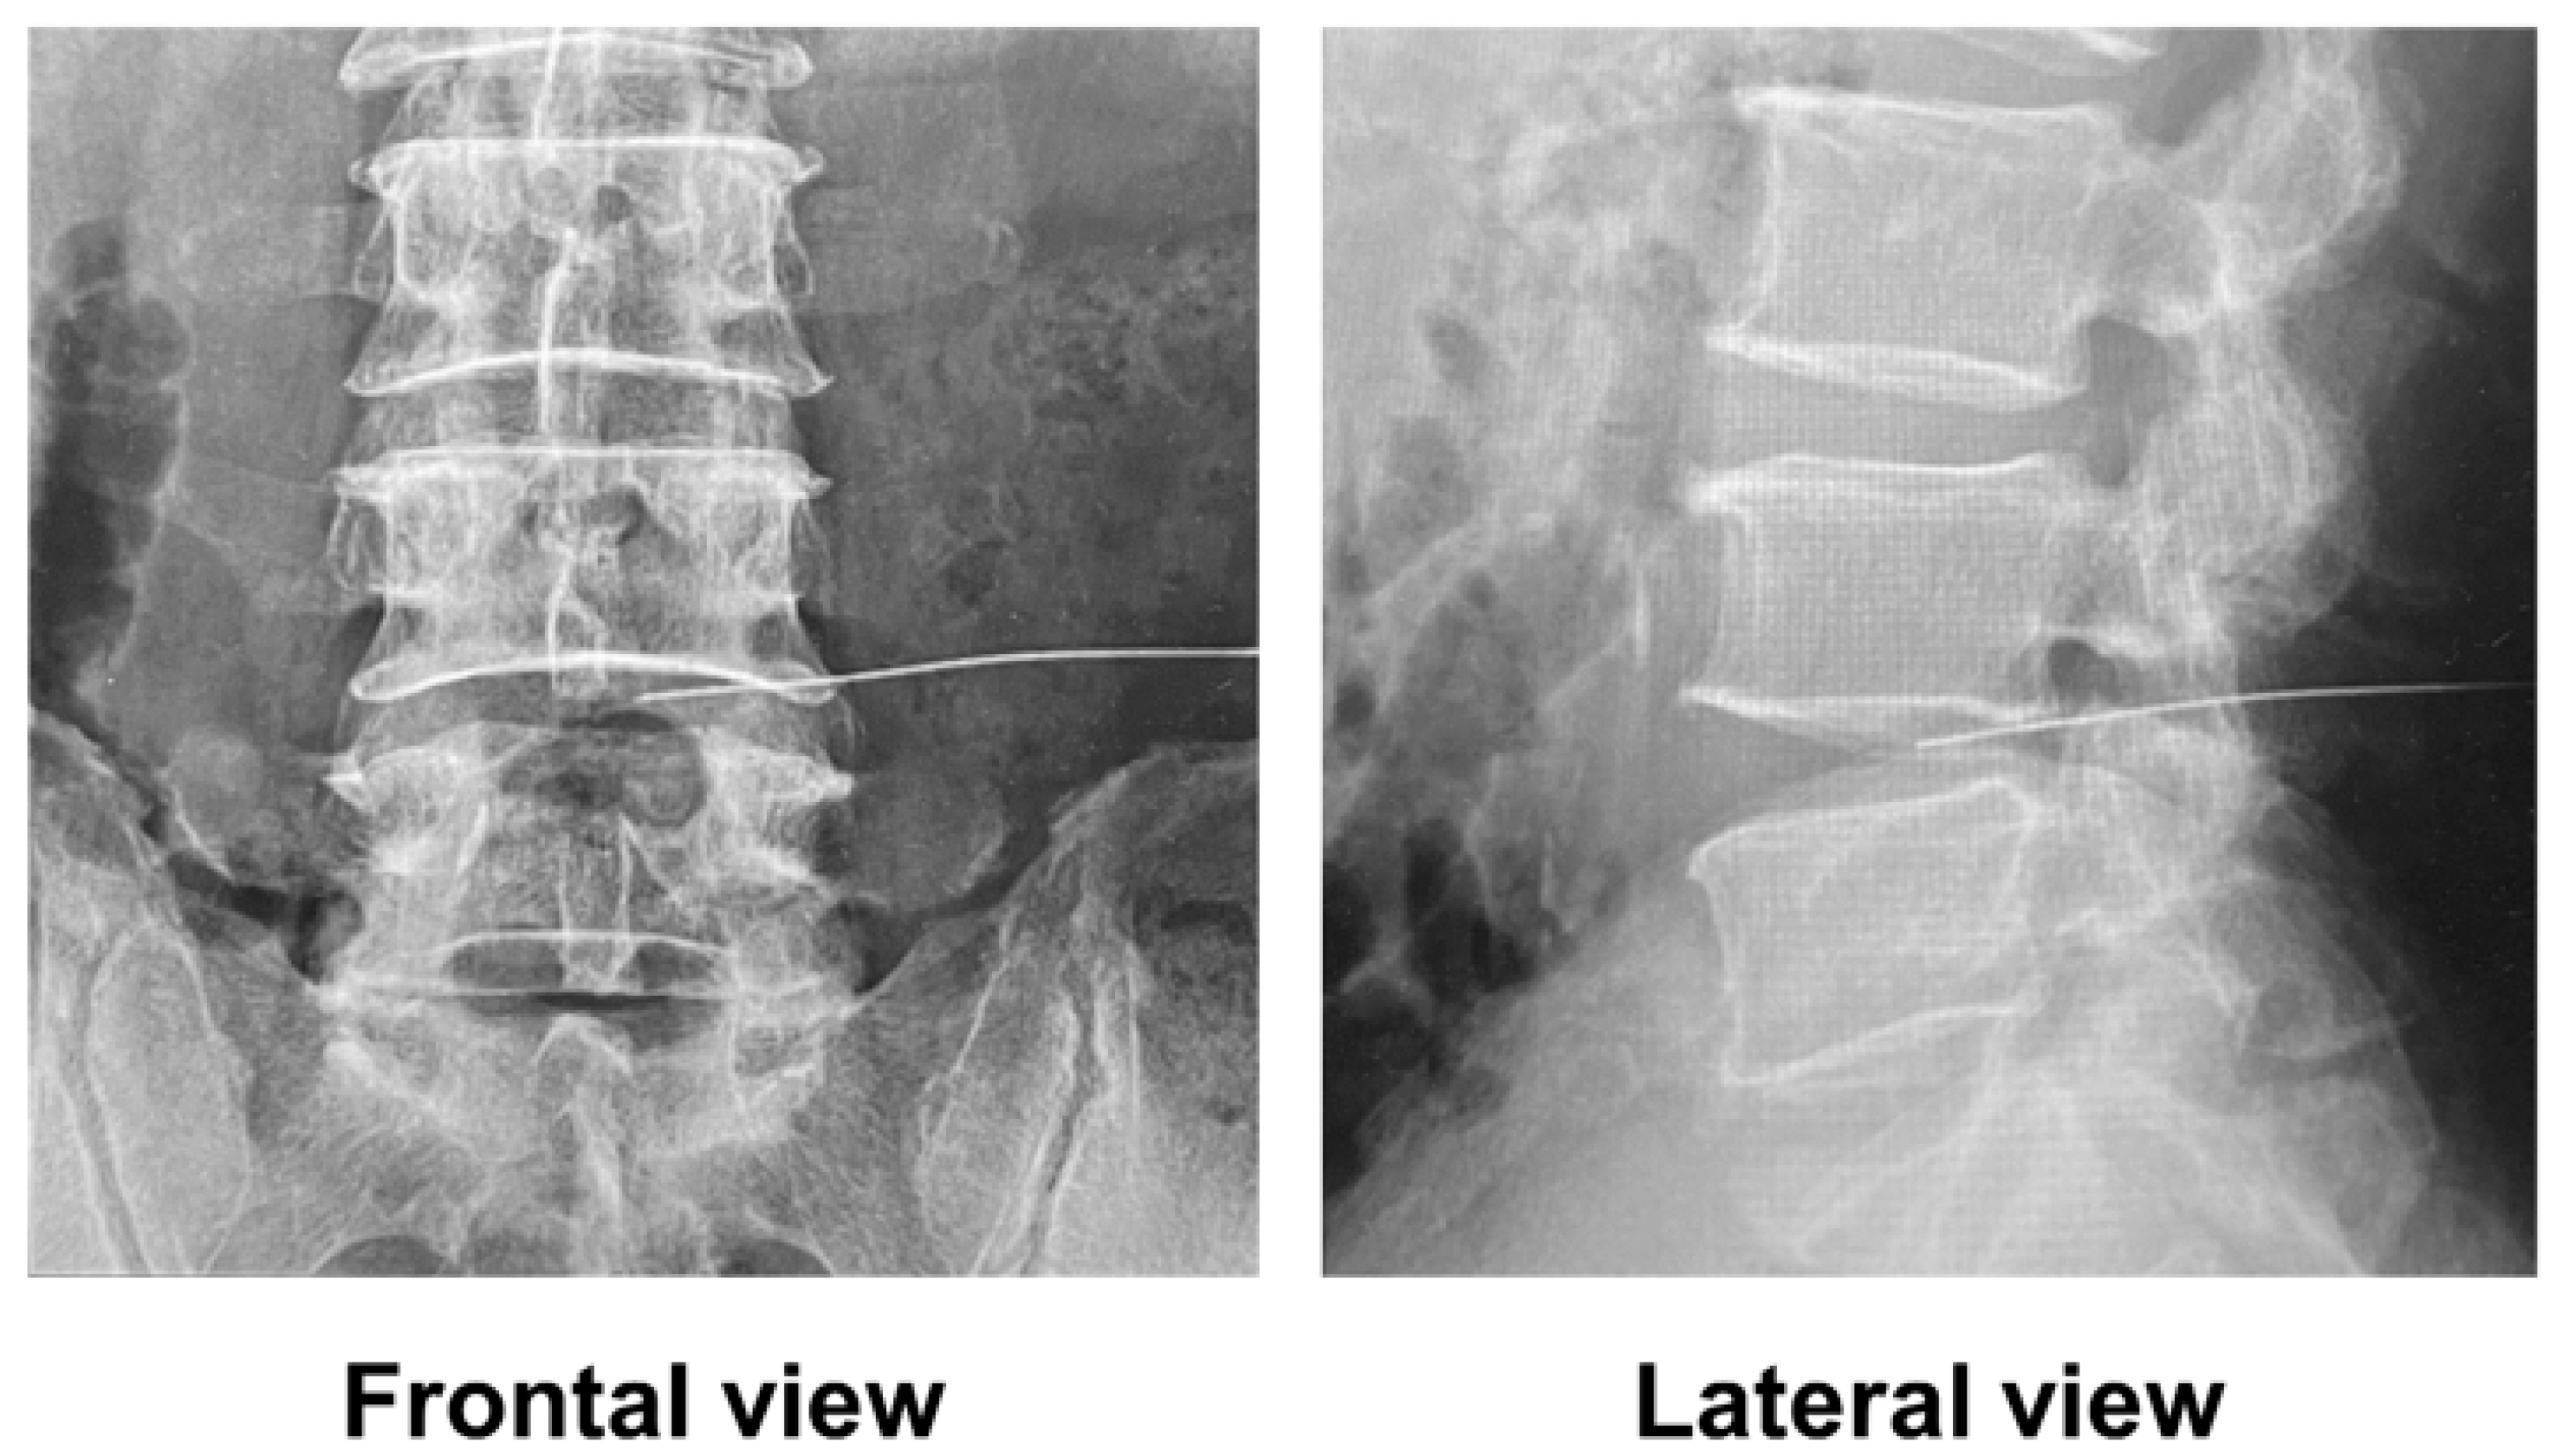

Treatment was performed in accordance with the guidelines for proper use provided by the pharmaceutical company (Kaken Pharmaceutical, Tokyo, Japan). In accordance with the protocol, the patients were admitted to the hospital, and the procedure was conducted in a fluoroscopy room. The patients were placed in the prone position, and fluoroscopic frontal and lateral views of the lumbar spine confirmed that the needle tip was approximately at the center of the intervertebral disc (Figure 1). Afterward, the needle was inserted into the disc from the herniated side in an oblique view of the lumbar spine, and condoliase was injected. Patients were observed at rest for at least 3 h after treatment.

Figure 1.

Fluoroscopic images immediately before condoliase injection.